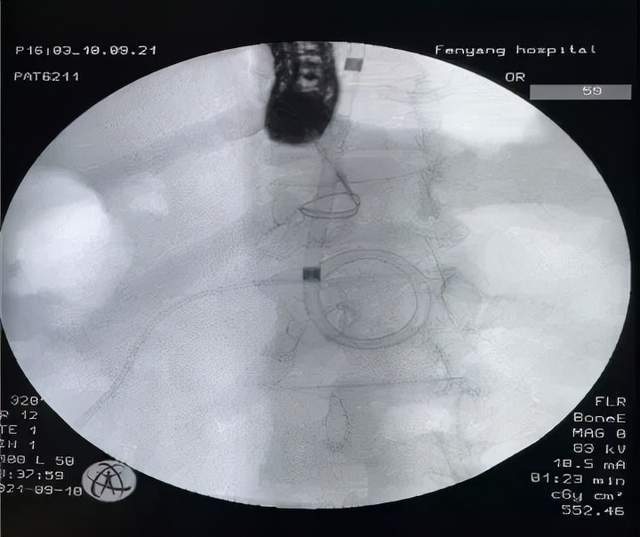

9月10日 , 在山西省汾阳医院消化内镜团队与麻醉科共同协作下 , 成功为一例急性胰腺炎后胰腺假性囊肿合并感染的患者实行了超声内镜(EUS)引导下胰腺假性囊肿穿刺引流术+ERCP(经内镜逆行胰胆管造影)胰管支架置入术 。

ERCP胰管支架置入术

【吕梁|新技术!山西省汾阳医院消化内科又一项联合技术填补吕梁空白】 首先进行常规内镜下逆行胰胆管造影(ERCP)检查 , 明确囊肿是否与主胰管相通 , 囊肿位置、大小、主胰管是否有狭窄 。 如囊肿与主胰管相通 , 则留置导丝在囊肿腔内 , 沿导丝置入大小合适的胰管支架 。 支架必须越过狭窄段 , 以达到充分引流的目的 。 该技术作为这一类胰腺假性囊肿的微创治疗手段 , 已在各大医院广泛开展 , 并取得良好疗效 。